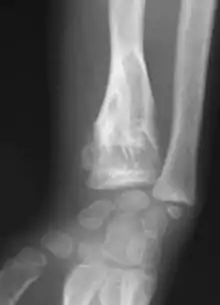

Abnormal bone growth such as shortening or thickening and deformity may be observed in patients of Ollier disease. These bone lesions are visible at birth using radiography but are usually not screened or examined for until clinical manifestations present during early childhood. However, some patients may exhibit no signs of any symptoms.[1] One study found thirteen to be the mean age of diagnosis in patients with Ollier disease. In an X-ray, there would normally be the presence of several homogeneous lesions of an oval or elongated shape with bone edges that are slightly thickened.[3] With age, these lesions may calcify and appear as diffusely minute spots or stippled. Fan-like septations or streaks would be indicative of the presence of several enchondromas. Early detection and consistent and repeated monitoring is important in order to prevent and treat any potential bone neoplasms.

Magnetic resonance imaging (MRI), ultrasound, and scintigraphy are generally not practical for diagnostic purposes. X-rays are not as effective in the monitoring or evaluation of enchondromas due to frequent localized changes also sometimes due to the large number of enchondromas. MRI can sometimes however be used to monitor and evaluate symptomatic lesions in the case of potential malignant transformations.